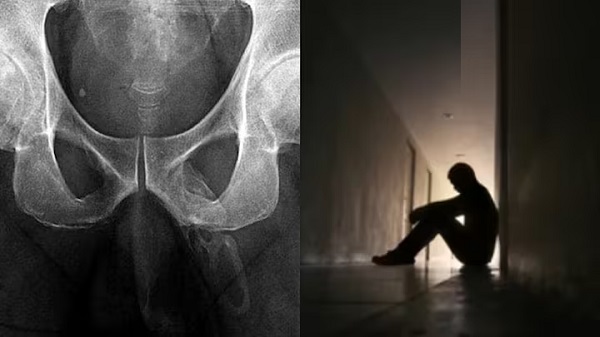

नई दिल्ली । चिकित्सा क्षेत्र (Medical field) में एक और हैरान करने वाला मामला सामने आया है। एक व्यक्ति (Person) का लिंग हड्डी (Bone) में तब्दील होता जा रहा है। जी हां, मेडिकल की इस रेयर कंडीशन को लेकर डॉक्टर्स भी हैरान हैं। दरअसल, 60 साल का आदमी अपने नितंबों के बल गिर गया था जिसके बाद उसके घुटनों में दर्द होने लगा। यह समस्या लेकर वह डॉक्टर के पास गया, जहां जांच के दौरान इस दुर्लभ स्थिति के बारे में जानकारी मिली। डॉक्टर्स को पता चला कि मरीज का लिंग हड्डी में बदलता जा रहा है। मेडिकल लाइन में इसे पेनाइल ऑसिफिकेशन के रूप में जाना जाता है।

पेनाइल ऑसिफिकेशन के चलते प्राइवेट पार्ट में हड्डी निकल आती है। इस बीमारी में शरीर के नर्म अंगों में कैल्शियम जमा होना शुरू हो जाता है जिससे एक्स्ट्रा हड्डी निकलने लगती है। ऐसी स्थिति में अक्सर मरीज को दर्द का एहसास नहीं होता है। यह बीमारी आघात या गठिया से जुड़ी हो सकती है। डॉक्टर्स के मुताबिक, यह समस्या तब होती है जब लिंग के कोमल ऊतकों में कैल्शियम जमा हो जाता है। इससे आगे चलकर पुरुष का लिंग बोनी एक्स्ट्रास्केलेटल संरचना का रूप लेने लगता है।

रिपोर्ट के मुताबिक, इस मामले में डॉक्टर्स ने जब मरीज को लिंग से जुड़ी समस्या के बारे में बताया तो वह अस्पताल छोड़कर चला गया। उसने आगे की जांच और इलाज कराने से भी इनकार कर दिया। लाइव साइंस के अनुसार, इस बीमारी में राहत पाने के लिए इंजेक्शन या दर्द निवारक दवाओं का इस्तेमाल किया जाता है। लिंग में कैल्सीफिकेशन का इलाज शॉक-वेव थेरेपी के जरिए किया जाता है। रिपोर्ट में बताया गया कि 40 से 70 वर्ष की आयु वाले लोगों को इस समस्या से ग्रस्त होने का खतरा अधिक रहता है। हालांकि, इस बीमारी की चपेट में किसी भी आयु का व्यक्ति आ सकता है।